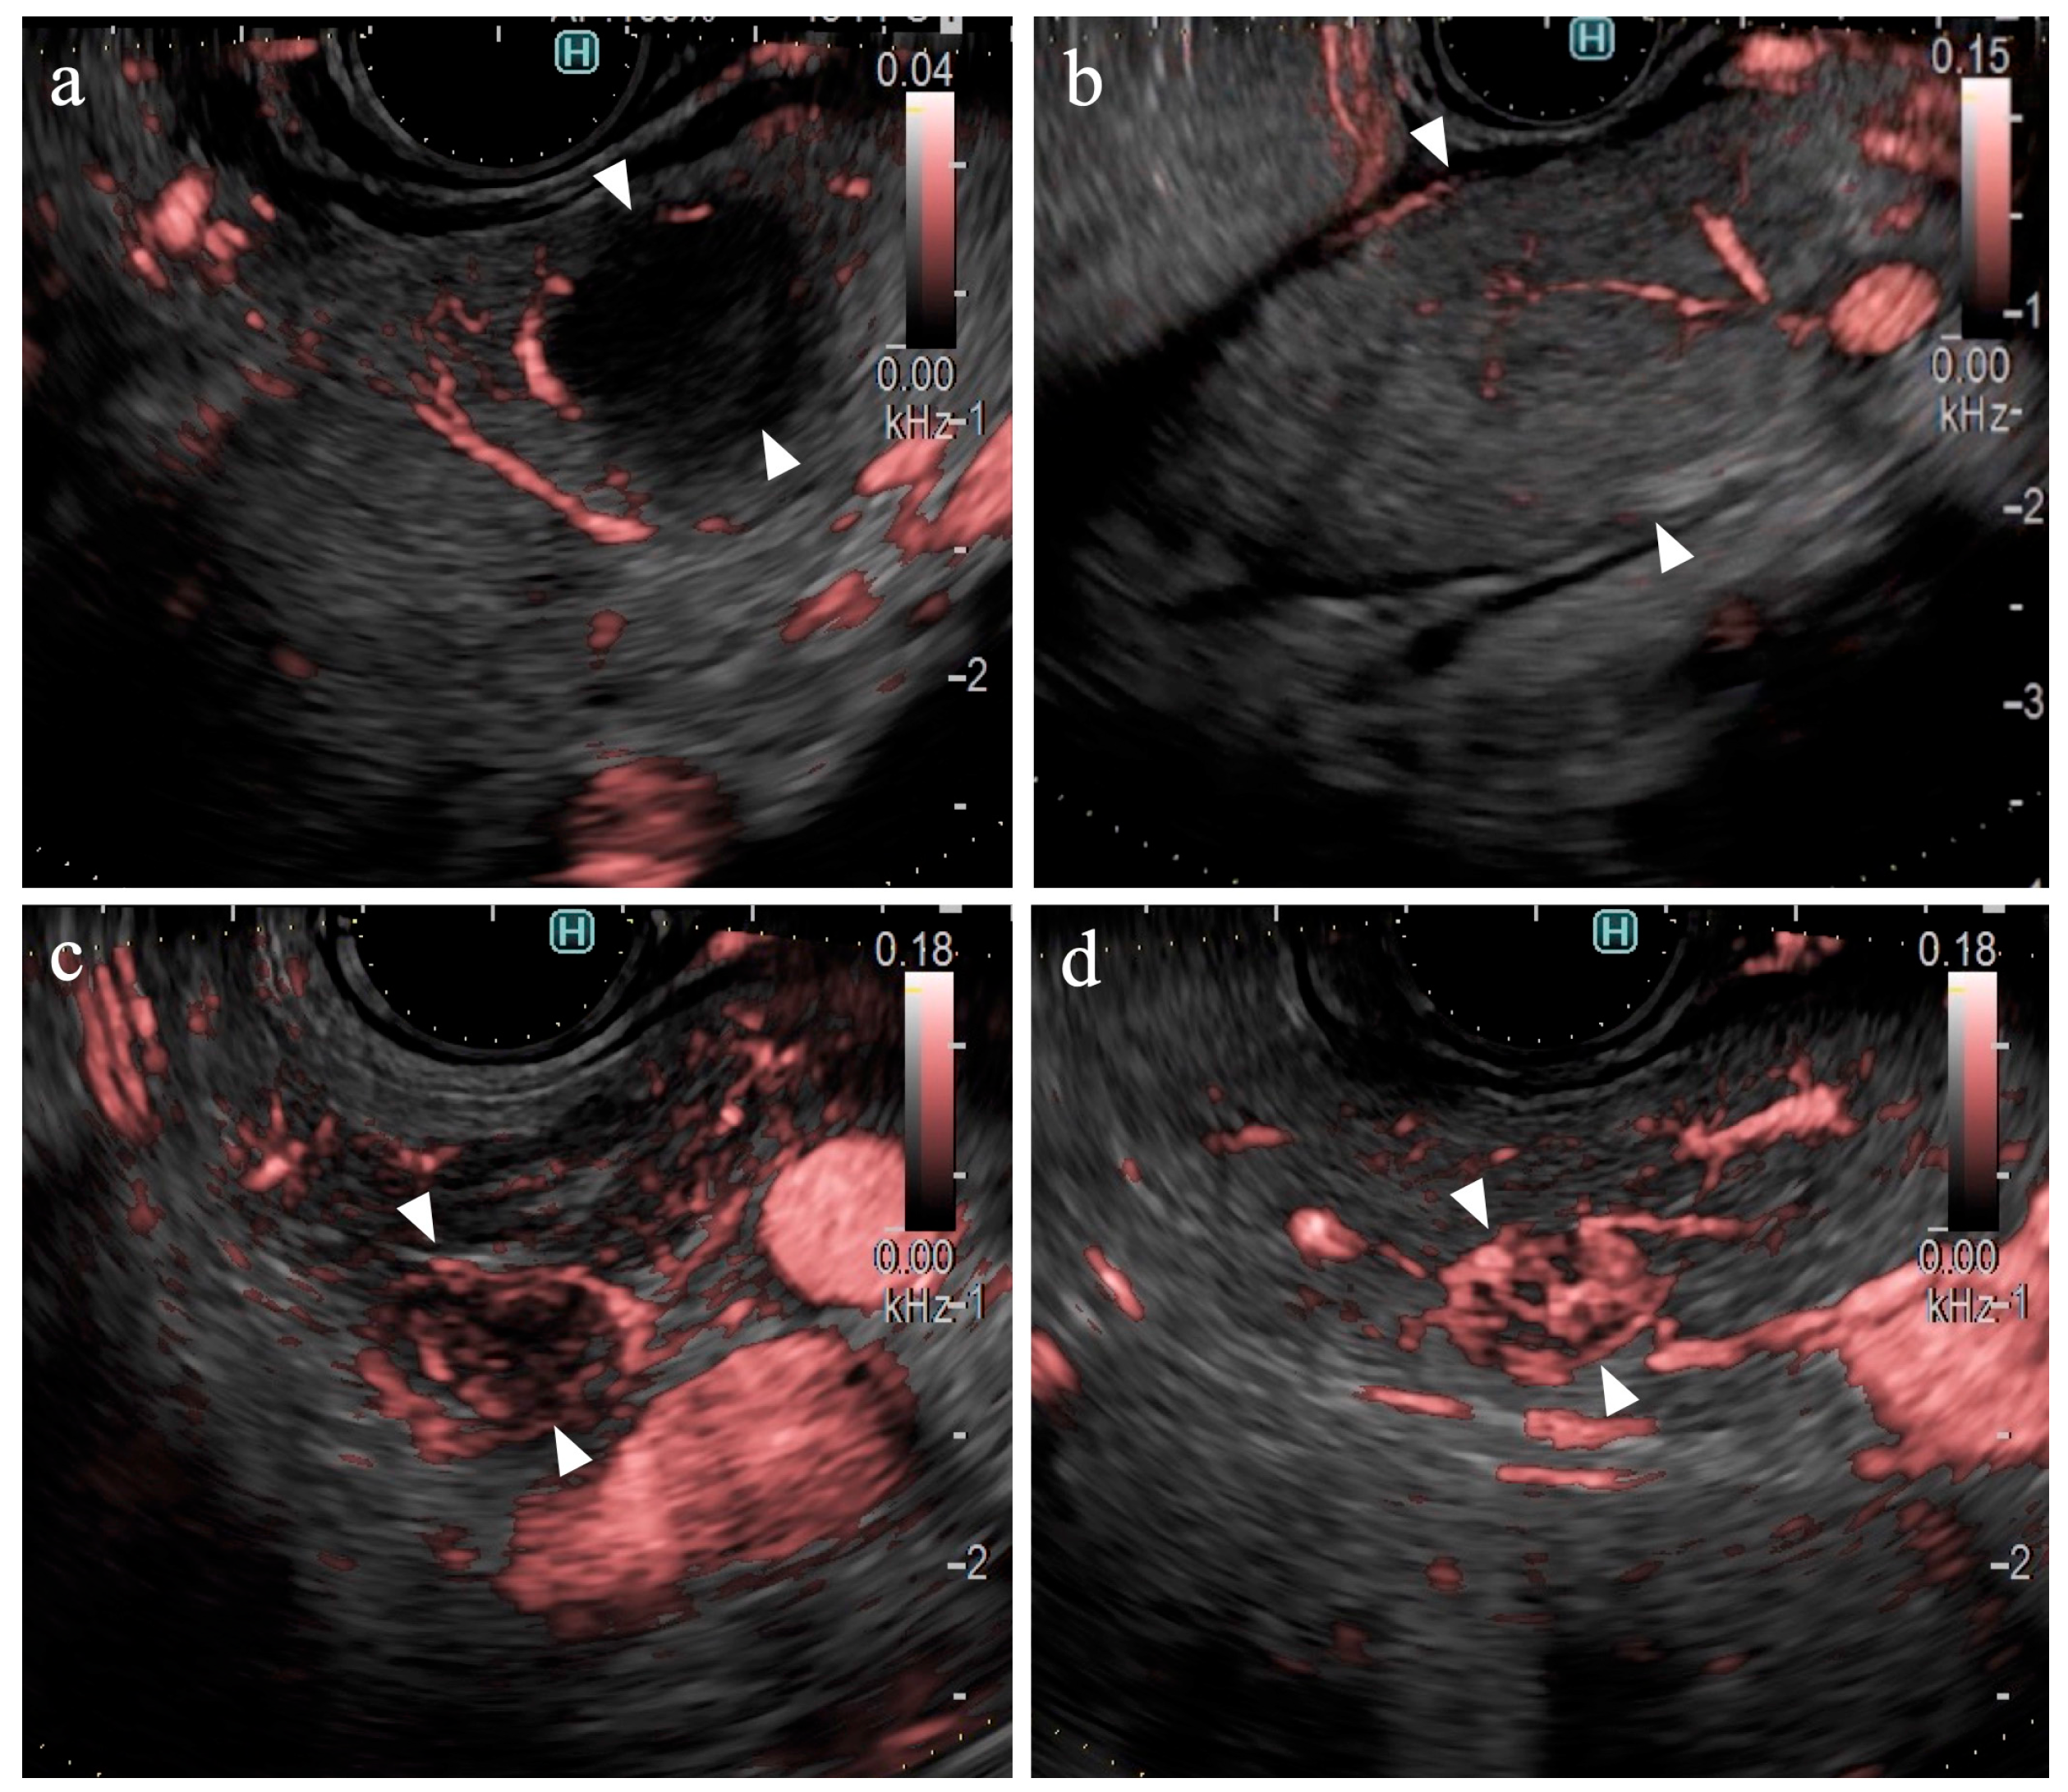

Findings of Pancreatic Cancer

Table 2 presents the result of the univariate analysis of the characteristics and findings of pancreatic cancer and other lesions. Pancreatic cancer was observed significantly more frequently in the pancreatic head (54%, p=0.013) and in areas deeper than 25 mm (63%, p=0.042). The number of large SPLs (> 20 mm) was greater in patients with pancreatic cancer than in other types of pancreatic lesions; however, the difference was not statistically significant. The majority of lesions were classified as hypoechoic lesions on B-mode (98% (102/104), p=0.473). The borders were “well-defined” in 70% of the pancreatic cancer lesions and 81% of other types of lesions (p=0.362). “Irregular contour” and “heterogenic internal echo” were observed in 88% (73/83) and 83% (69/83) of pancreatic cancer lesions, respectively (p < 0.01). eFLOW detected the presence of vessels in 27% (28/104) of lesions only. The shape and distribution of the vessels were classified in cases where vessels were present within the lesion; however, no significant differences were observed. DFI detected the presence of vessels in 96% (100/104) of the lesions. Thus, the detection rate of DFI was significantly higher than that of eFLOW (p < 0.01). Four lesions without vessels were classified as “hypovascular”. Hypovascular lesions were significantly more frequent in patients with pancreatic cancer (p < 0.01). The distribution and shape of the vessels were evaluated in the 100 cases where vessels were present within the lesions. Pancreatic cancer lesions were accompanied by “peritumoral” and “spotty” vessels in 84% (66/79) and 86% (68/79) of cases (Figure 4a), respectively, significantly more than in other lesions, presenting 38% (8/21) and 43% (9/21) of cases, respectively (p < 0.01).

Findings on Lesions Other Than Pancreatic Cancer

Table 4 presents the findings in the NEN (n=6) and MFP (n=9) groups. No significant differences were observed between the two groups in terms of lesion characteristics. All lesions were hypoechoic on B-mode. No significant differences were observed between the B-mode and eFLOW findings. DFI could visualize vessels within the SPLs in all lesions. Notably, 83% (5/6) of the NEN lesions were hypervascular, whereas all MFP lesions were hypovascular (Figure 4b), with a statistically significant difference (p < 0.01).

The findings of this study demonstrate the utility of DFI for purposes other than the differential diagnosis of SPLs. DFI enabled the identification of small hypervascular lesions within 10 mm, which was unexpected (Figure 4c, 4d). The frame rate of DFI is higher than those of B-mode and eFLOW; thus, DFI can be used as a screening evaluation for patients with Multiple Endocrine Neoplasia type 1 or von Hippel-Lindau disease [39,40]. Hypersensitivity to vascular structures aided the avoidance of thick vessels during the EUS fine-needle biopsy (EUS-FNB) procedure (Figure 5). DFI, rather than eFLOW, can be used to define the vessels more precisely in patients with NEN. This technique enables the effective acquisition of tissue samples without major bleeding. The absence of linear vessels in pancreatic cancer lesions can aid the detection of tumor margins (Figure 6). A pancreatic cancer lesion without a detectable margin was observed on B-mode and eFLOW in this case, and the initial EUS-FNB result was a false negative. Subsequently, DFI was performed, and the normal vessels in the surrounding pancreatic parenchyma near the tumor margin disappeared. The diagnosis was confirmed by puncturing the areas without vessels on DFI. Thus, DFI can be considered a novel tool for determining the differential diagnosis of pancreatic cancer in the future.

Figure 4. Vessel images of Detective Flow Imaging. (a) Pancreatic cancer (b) Mass forming pancreatitis (c) Neuroendocrine neoplasm (d) Metastatic tumor (Renal cell carcinoma).